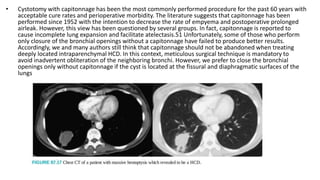

• Cystotomy with capitonnage has been the most commonly performed procedure for the past 60 years with

acceptable cure rates and perioperative morbidity. The literature suggests that capitonnage has been

performed since 1952 with the intention to decrease the rate of empyema and postoperative prolonged

airleak. However, this view has been questioned by several groups. In fact, capitonnage is reported to

cause incomplete lung expansion and facilitate atelectasis.51 Unfortunately, some of those who perform

only closure of the bronchial openings without a capitonnage have failed to produce better results.

Accordingly, we and many authors still think that capitonnage should not be abandoned when treating

deeply located intraparenchymal HCD. In this context, meticulous surgical technique is mandatory to

avoid inadvertent obliteration of the neighboring bronchi. However, we prefer to close the bronchial

openings only without capitonnage if the cyst is located at the fissural and diaphragmatic surfaces of the

lungs